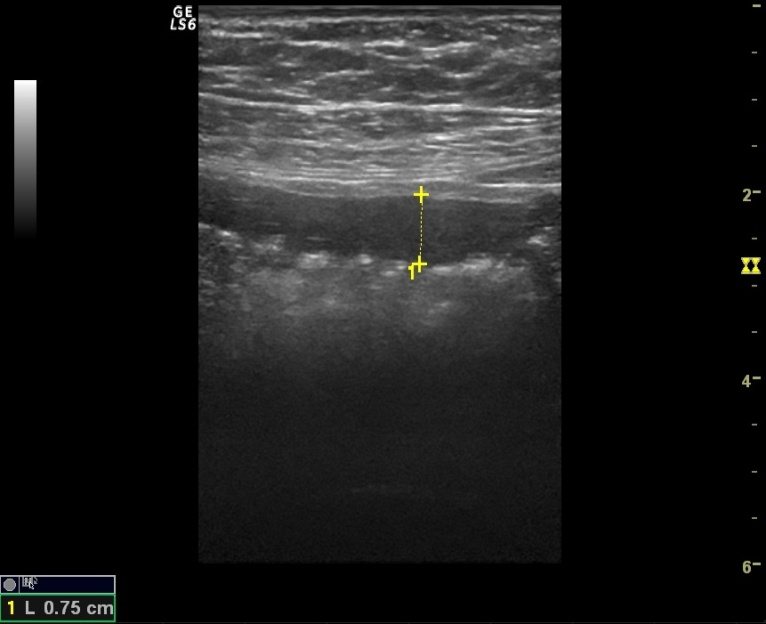

Acute abdominal pain is one of the most common conditions encountered in the emergency department. The differential diagnosis of acute abdominal pain is extensive and identifying the underlying etiology can be challenging. We report a case of acute transient ischemic jejunitis due to symptomatic isolated superior mesenteric artery dissection in a patient with no cardiovascular risk factors or autoimmune diseases. Symptomatic isolated superior mesenteric artery dissection is a rare cause of acute abdominal pain usually treated in the surgical department. The patient had criteria for conservative treatment and rapidly recovered. We highlight a rare condition which should be taken into account for the differential diagnosis of acute abdominal pain.